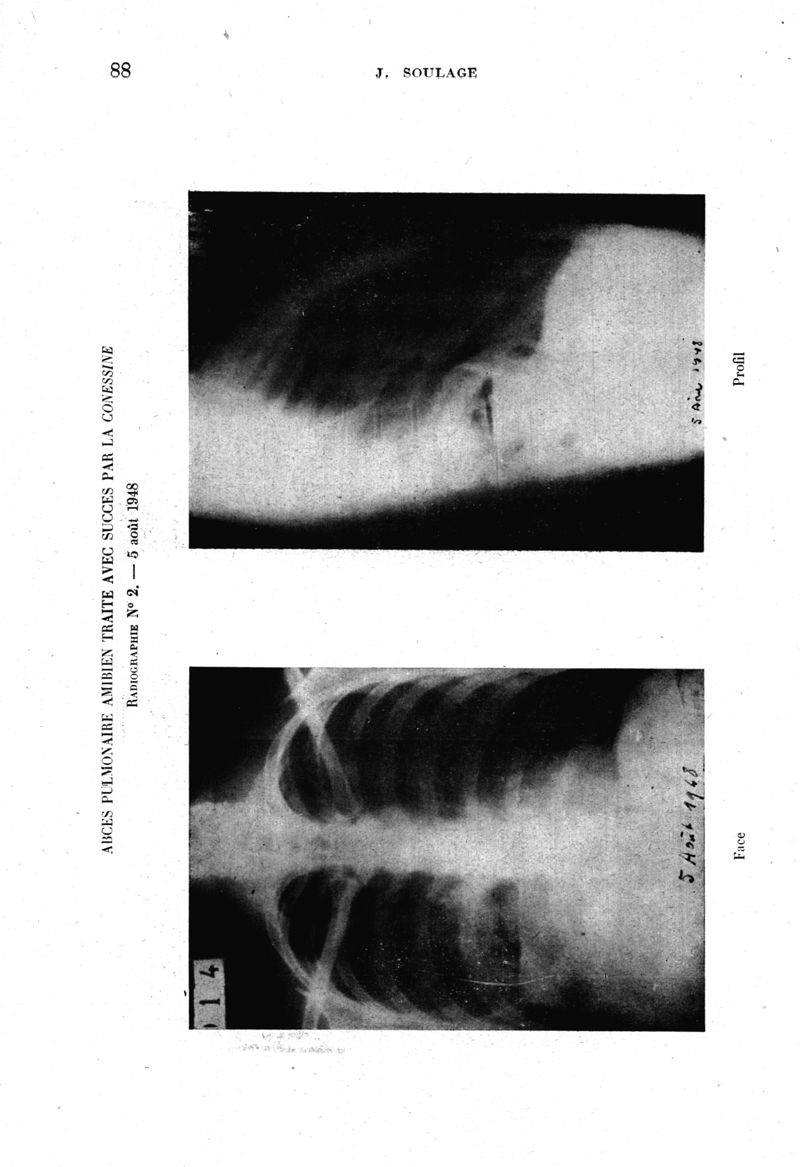

Médecine tropicale : Revue du corps de santé colonial

. - Marseille : Ecole d'application du service de santé des troupes coloniales, 1949.